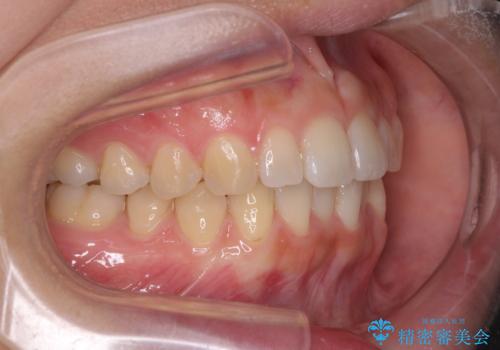

インプラントによる補綴治療とインビザライン矯正

- 抜歯が必要と診断された奥歯を気にして来院された患者様です。

抜歯の上インプラントによる補綴治療を行うこととなりましたが、前歯の叢生も気になるとのことで並行して矯正治療を行うこととしました。

歯列不正は軽微であったので、インビザラインによる矯正治療とし、矯正治療中にインプラント埋入を行う予定としました。

痛みがないので、ボロボロのまま放置していましたが、抜歯後は汚れが溜まりにくくなりスッキリとしたようです。

前歯のデコボコも解消され、ブラッシングが楽になりました。